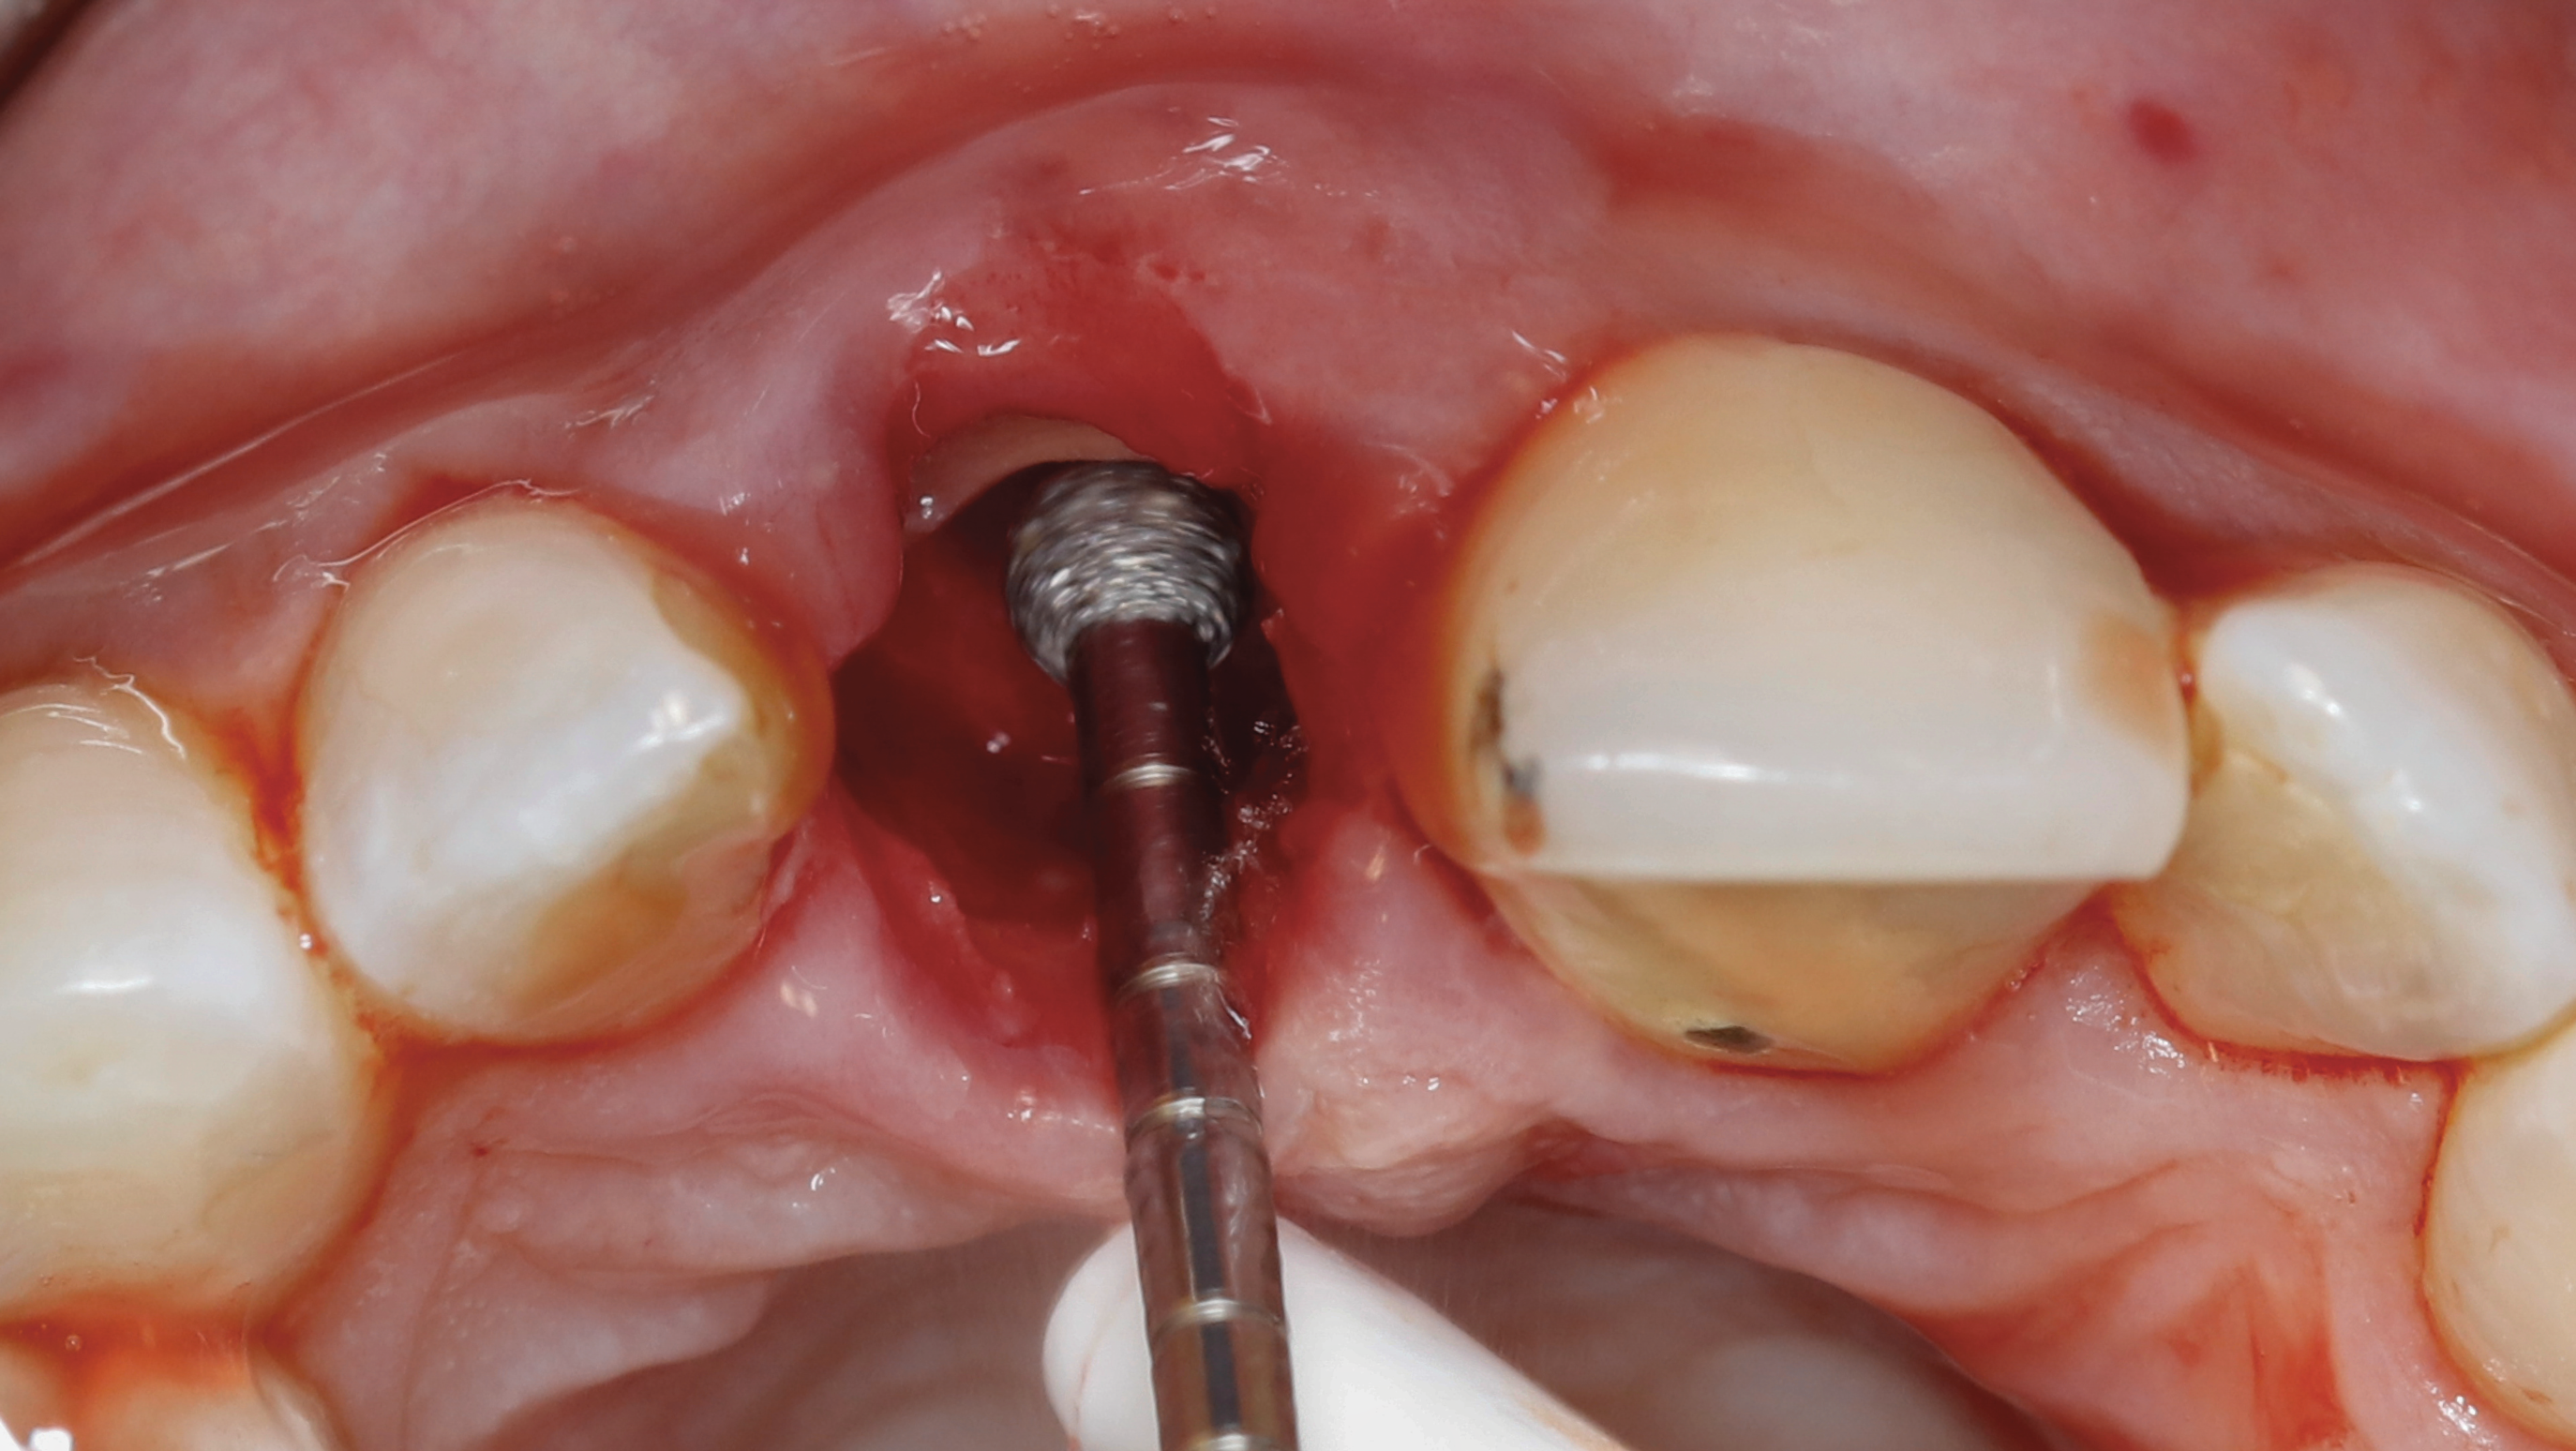

Fig 5. SPOT Step 1: After the clinical crown is removed, a high-speed diamond bur (Meisinger 801H-029) is used to hollow out the center of the tooth 2 mm to 3 mm subgingivally leaving a 1 mm rim of dentin around the root circumference.

Figure 5

Step 1 - Hollow out the tooth center: A 3-mm diameter round diamond bur (Meisinger 801H-029) is used to hollow out the middle of the tooth 2 mm to 3 mm subgingivally, leaving a 1 mm ring of dentin around the circumference of the root (Figure 5).